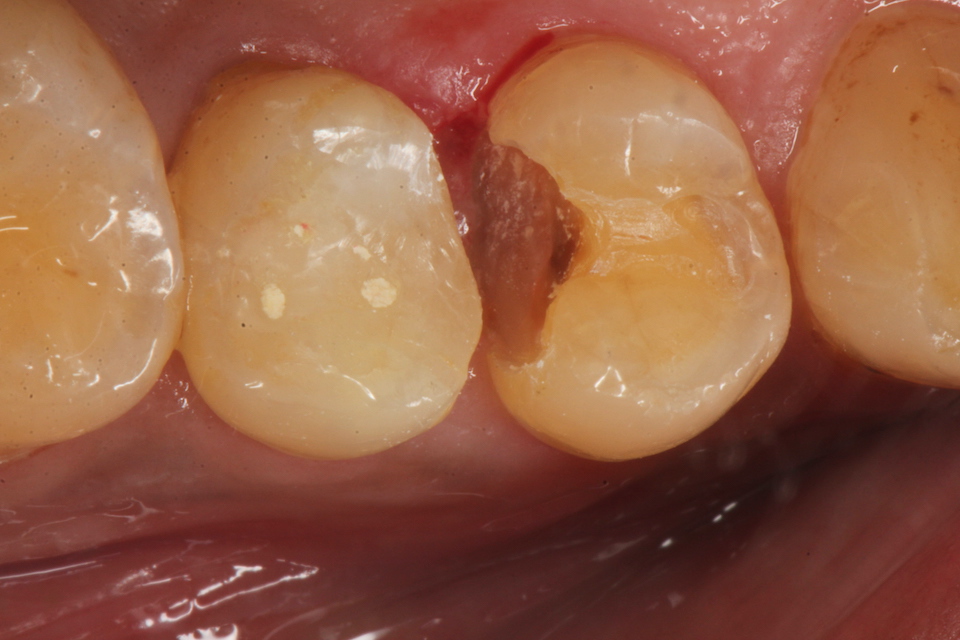

50代男性、右上45、インレー破折後の2次カリエス、咬合性外傷

露髄ギリギリなのだが、自覚症状はない。虫歯がある程度進むと染みたり痛みを感じにくくなる。それは虫歯は水素イオンの電導性がないからだ。水素イオンが歯髄の神経に到達すると痛みを感じるのだが、水素イオンの伝導は歯の主成分のハイドロキシアパタイトだけにしか起こらず、ハイドロキシアパタイトが壊れてしまった虫歯には水素イオンが伝導しない。

またこれに関連するのだが、一般に軟化象牙質(虫歯:ハイドロキシアパタイトが失われた象牙質)には細菌が侵入しているとされているが、実は細菌は全くいない。虫歯は細菌とは基本的には無関係なハイドロキシアパタイトの電気化学的な腐食だからだ。

咬合性外傷があるとスレあとが着く。